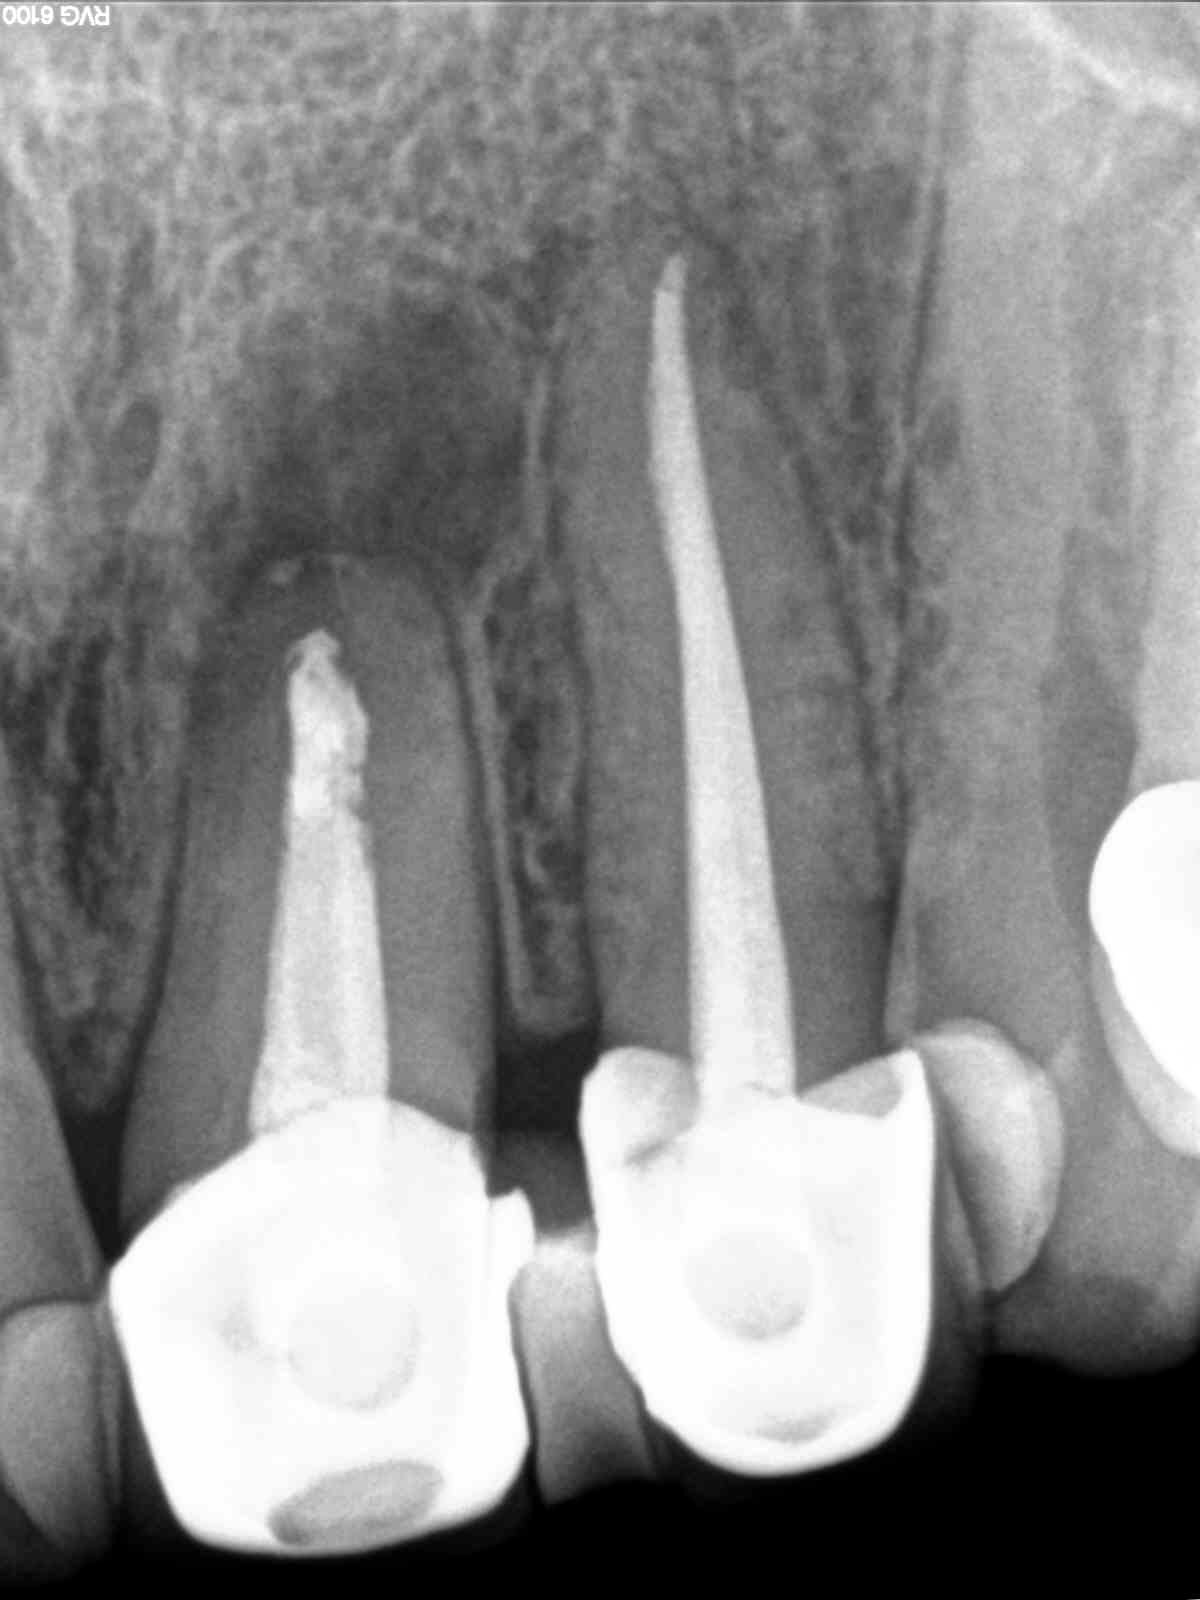

R1 Veröffentlicht 7. September 2015 am 1200 × 1600 in „2D vs. 3D“ oder „Thermafill, wo es nicht hingehört“